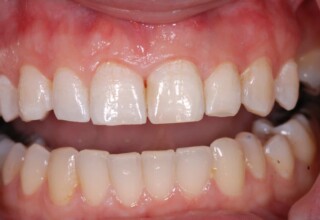

Porcelain Veneers

The best way to solve esthetic problems of the anterior teeth. They combine very little tooth grinding with very high esthetic performance. In the following extensive case anterior teeth presented with: old restorations, staining, poor shape, length and tooth –gingiva ratio. Meticulous diagnostic waxing was performed on study casts and temporary veneers were manufactured. Temporary veneers were used intraorally to evaluate the incorporated changes and to further modify and adjust were needed. When esthetics and function were approved by the patient and were satisfying for the operator the temporaries were used as a guide for the final porcelain veneers. The five final veneers on the upper anterior teeth restored the smile of the patient to almost perfection.

Initial appearance

Final appearance